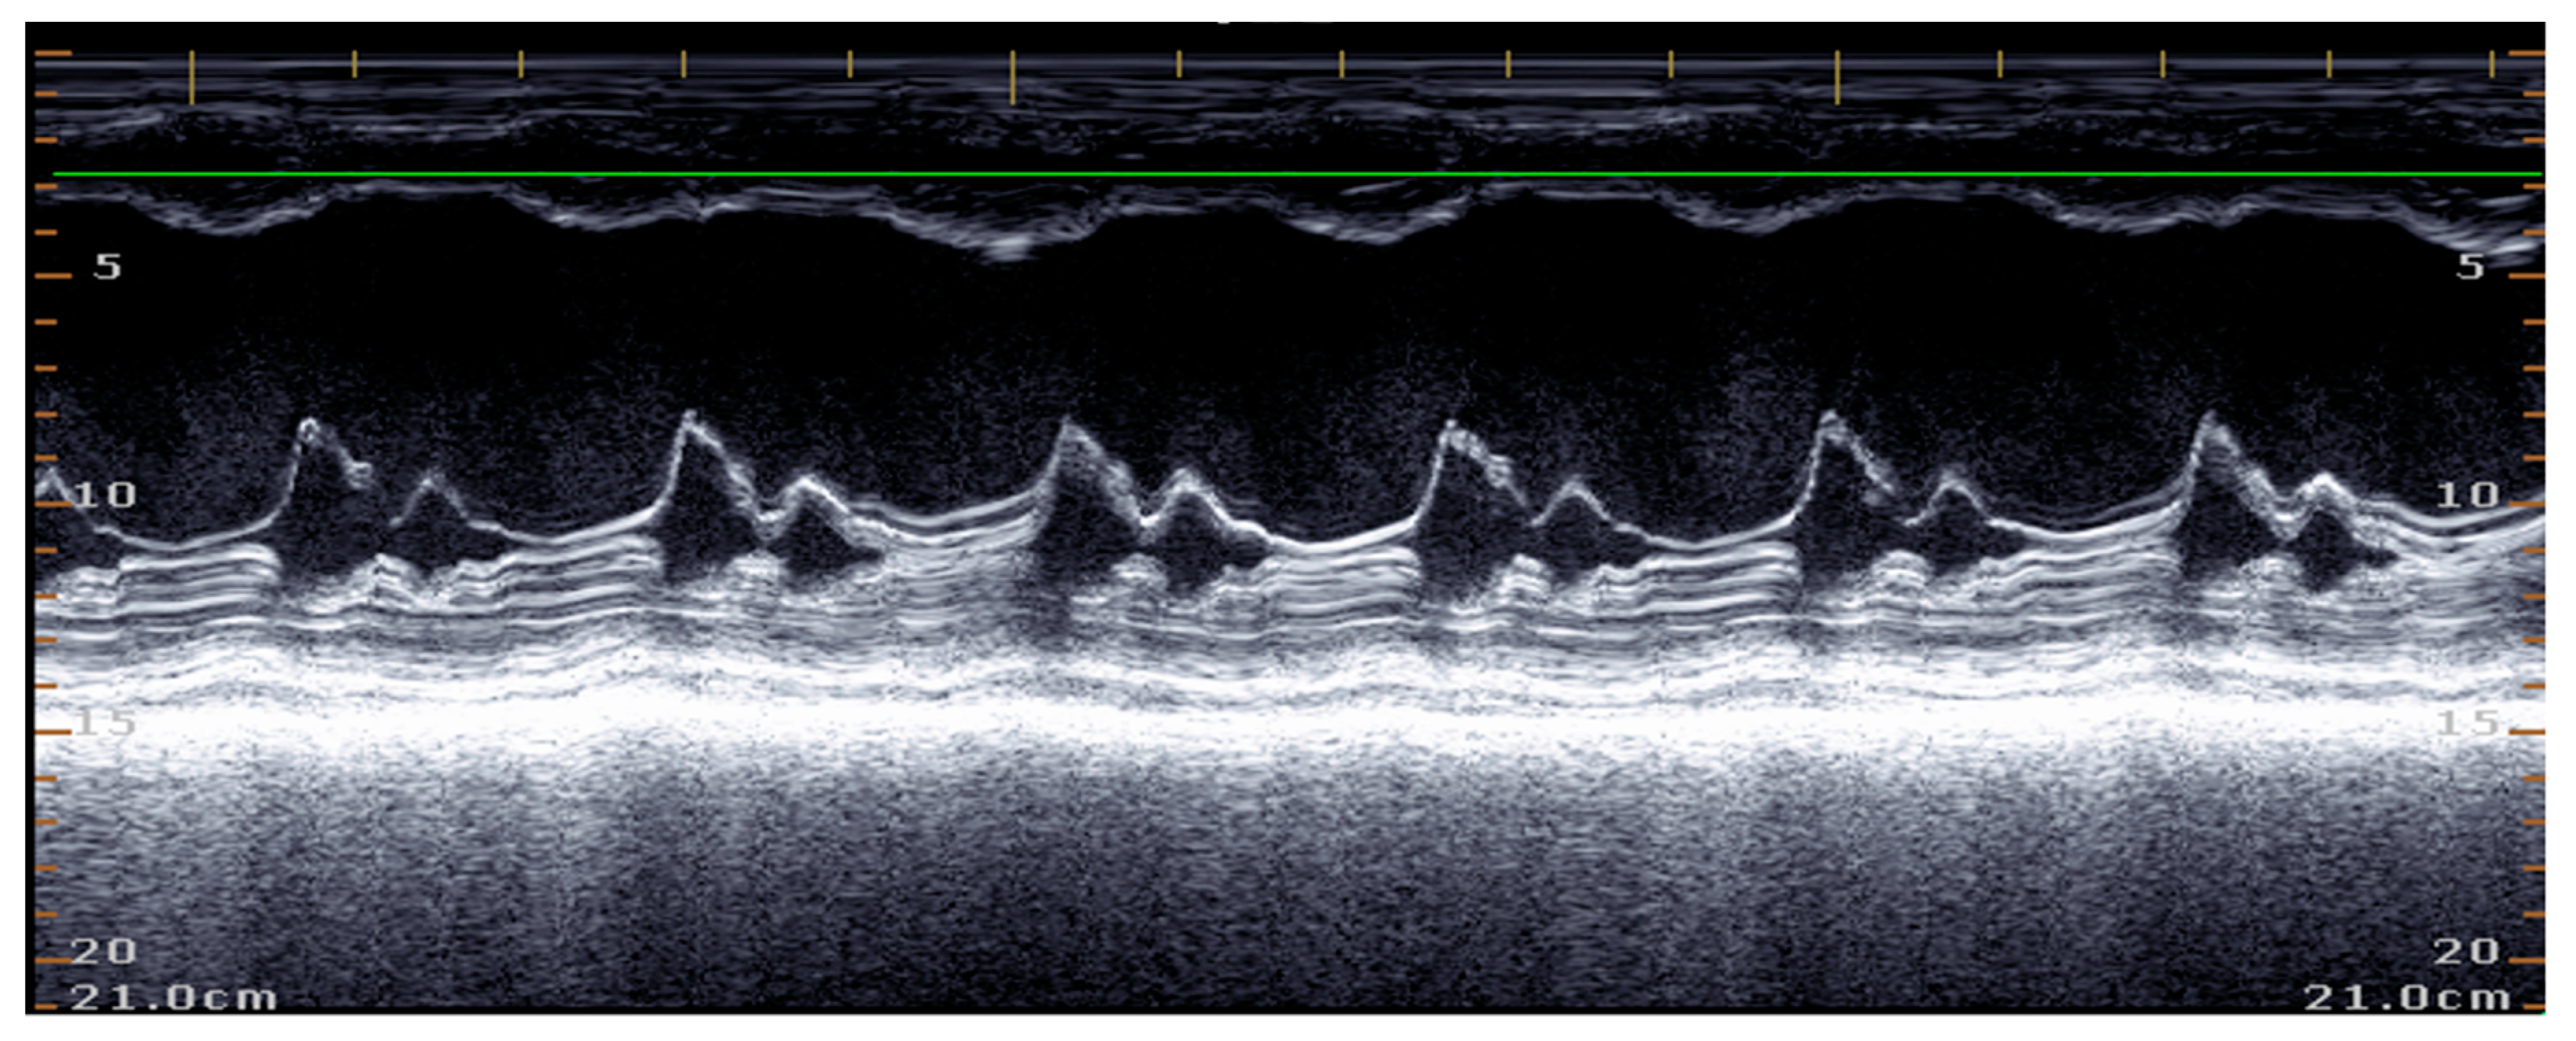

5.1.1. Measurement of Left Ventricular Volume by Simpson’s Method of Disks and Left Ventricular M-Mode

5.1.2. E-Point to Septal Separation or EPSS: An Echocardiographic Parameter for Accurate Assessment of Left Ventricular Performance

5.1.3. Sphericity Index (SI)